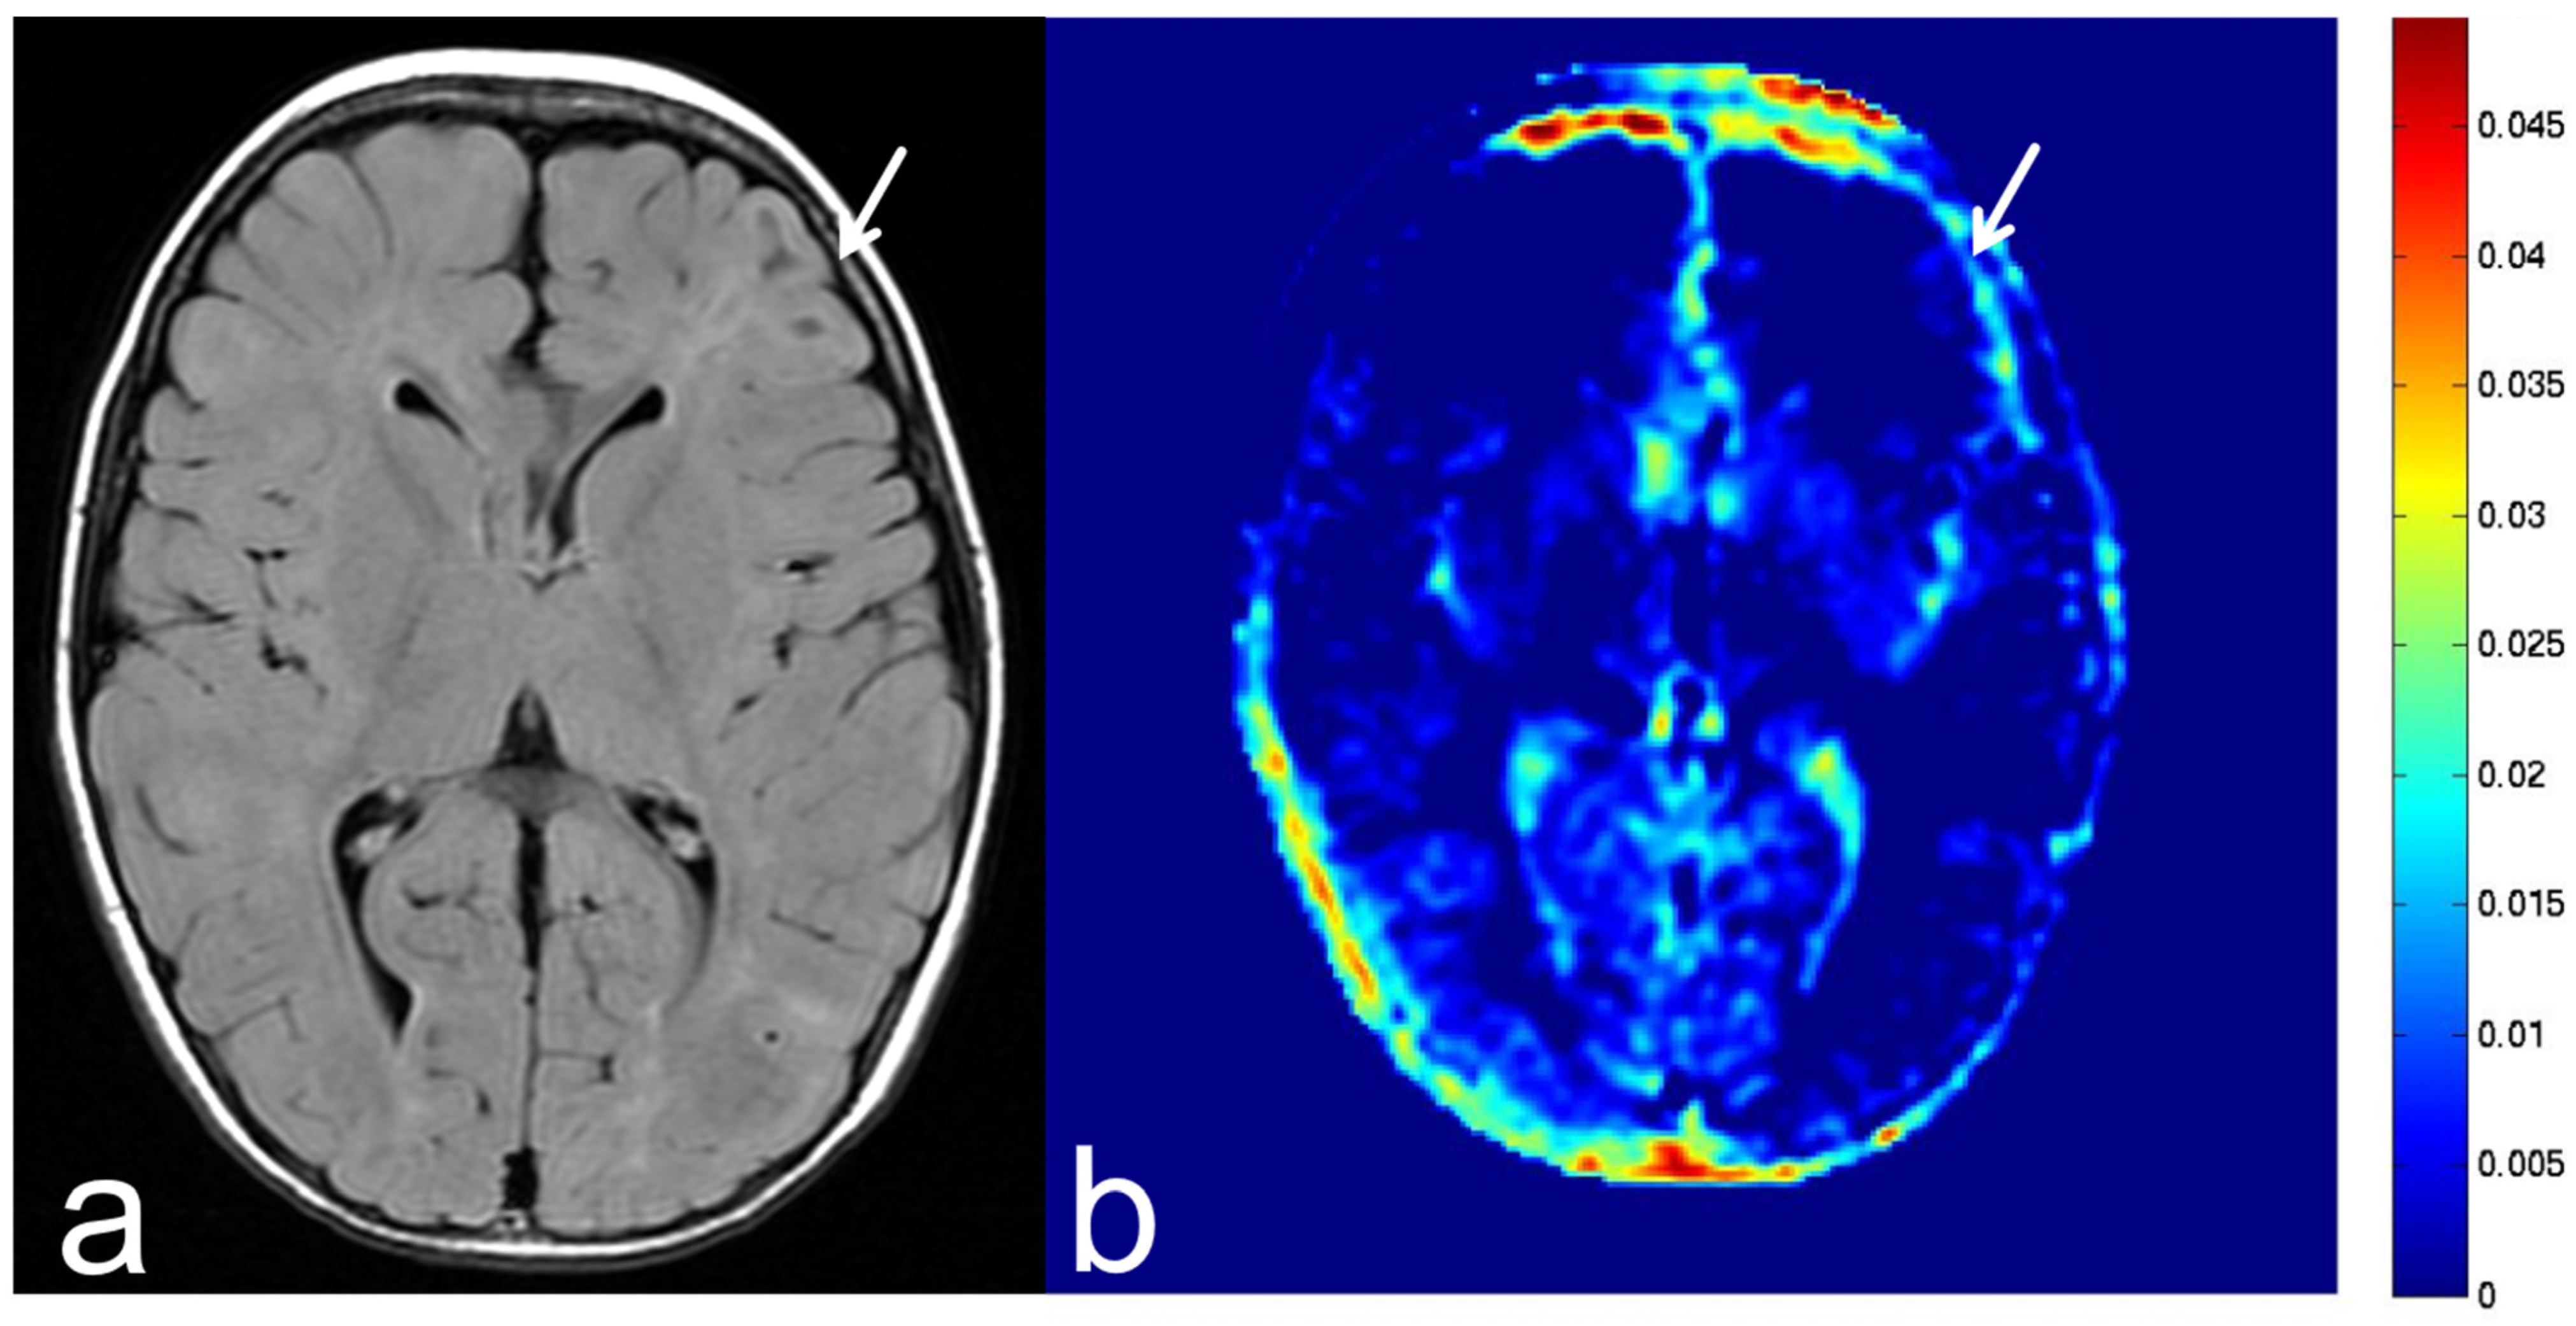

6. APT-CEST Imaging of Meningioma

7. APT-CEST Imaging of Benign Lesion